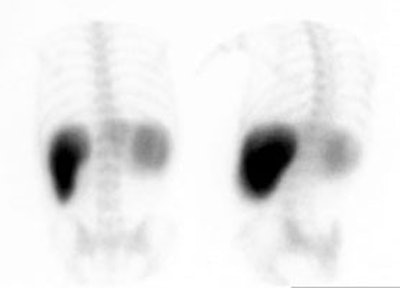

With a loss of functioning hepatic parenchyma (or liver blood flow) a "shift" in phagocytic function will result in enhanced colloid uptake by other reticuloendothelial tissue, especially the spleen and bone marrow. In severe hepatic failure, uptake in the lungs may occur. A spleen to liver ratio of greater than 2:1 is considered evidence of colloid shift [Zeisman quotes greater than 1.5:1 as abnormal]. Colloid shift is a non-specific finding and may be due to hepatocellular dysfunction (cirrhosis, passive congestion, chemotherapy), infection (hepatitis, mononucleosis, sepsis), or marrow activation. Some authors differentiate colloid shift (prominent splenic and bone marrow activity) from simple shift (reversal of the normal liver to spleen ratio).

Colloid shift: A posterior and posterior oblique image from a Tc-SC exam demonstrate markedly increased splenic activity in association with an enlarged spleen. The liver is small and bone marrow activity can also be seen. The extrahepatic reticuloendothelial accumulation of the tracer indicates hepatocellular dysfunction. |